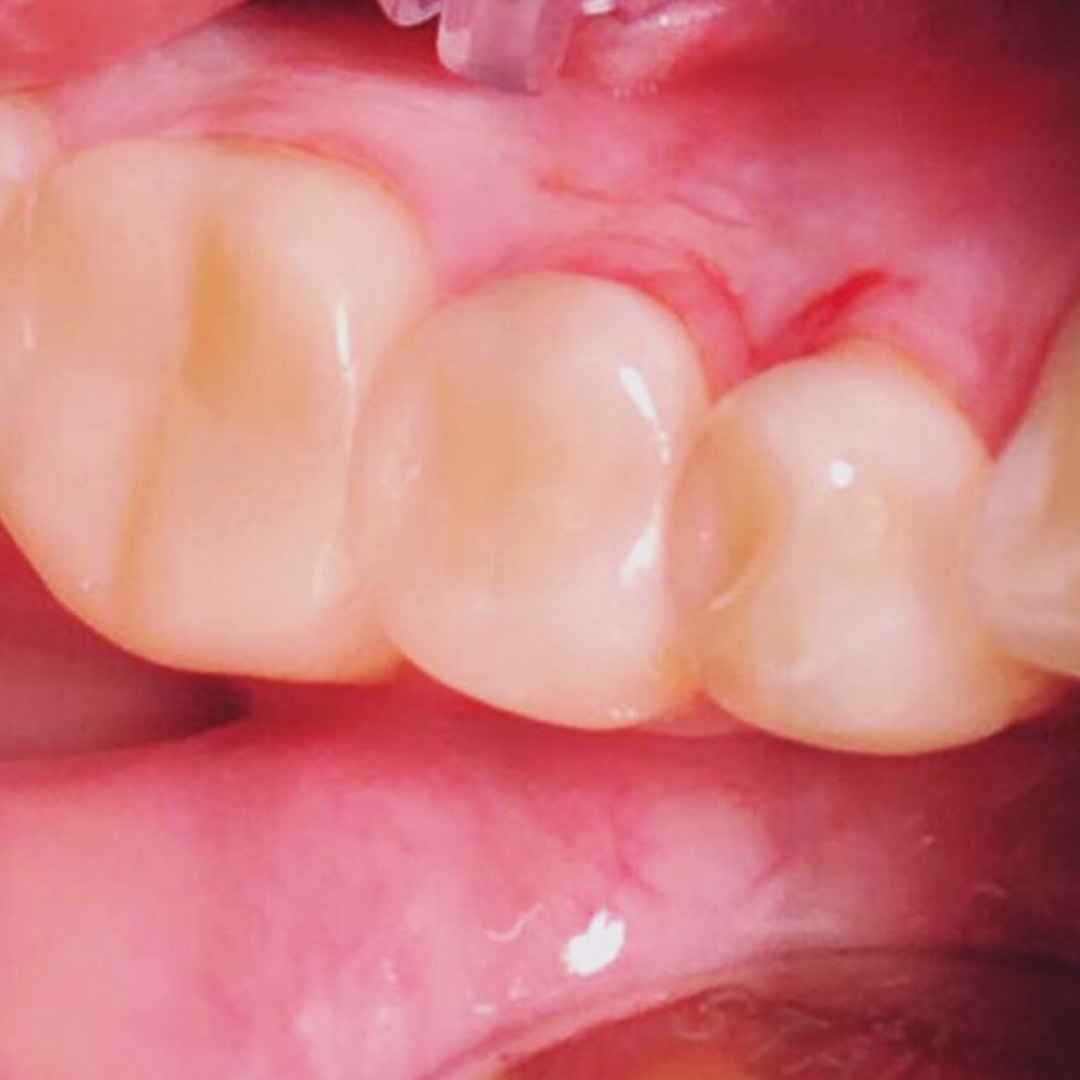

До и после лечения

Пациентка обратилась в «Стоматологию Комфорта» с жалобами на выпадение пломб зубов 44 и 45, болезненную реакцию на холодное и застревание пищи. В результате обследования врач Похилько Надежда Геннадьевна обнаружила глубокий кариес в районе зубов 44 и 45. Принято решение провести лечение с использованием композита светового отверждения Estelite.

- установка пломбы из композита светового отверждения Estelite.

Смотреть работуСрок лечения:90 минутСумма лечения:5 600 руб.